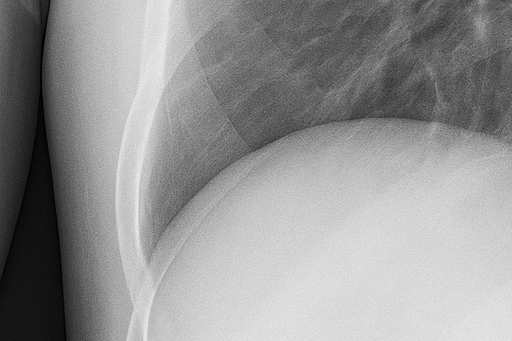

(2) 흉부 X선 검사

흉부 X선 촬영은 가장 기본적이고 신속한 진단 방법입니다. X선 영상에서 공기가 찬 부위는 검게 보이며, 허탈된 폐는 중심 쪽으로 쪼그라든 형태로 나타납니다. 이를 통해 폐 허탈의 범위와 기흉의 크기를 확인할 수 있습니다. 그러나 폐 상부의 작은 공기집(bleb)은 X선으로 잘 보이지 않아, 필요한 경우 흉부 CT 검사를 시행합니다.

(3) 흉부 CT(전산화 단층촬영)

CT 촬영은 폐 내부 단면을 자세히 보여주어 기흉의 원인과 위치를 정밀하게 파악할 수 있습니다. 특히 재발성 기흉이나 수술 후 추적관찰 환자에게 유용합니다. CT는 작은 공기집이나 폐포 손상, 흉막 유착 상태까지 세밀히 보여주어 수술 필요성을 판단하는 데 도움이 됩니다.